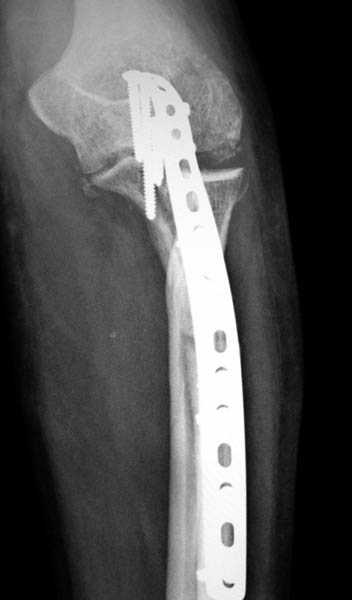

Здесь выставлены несколько случаев и варианты фиксации локтевого отростка, некоторые в комбинации с другими переломами.

1 вариант применен ACUMED локинг пластина